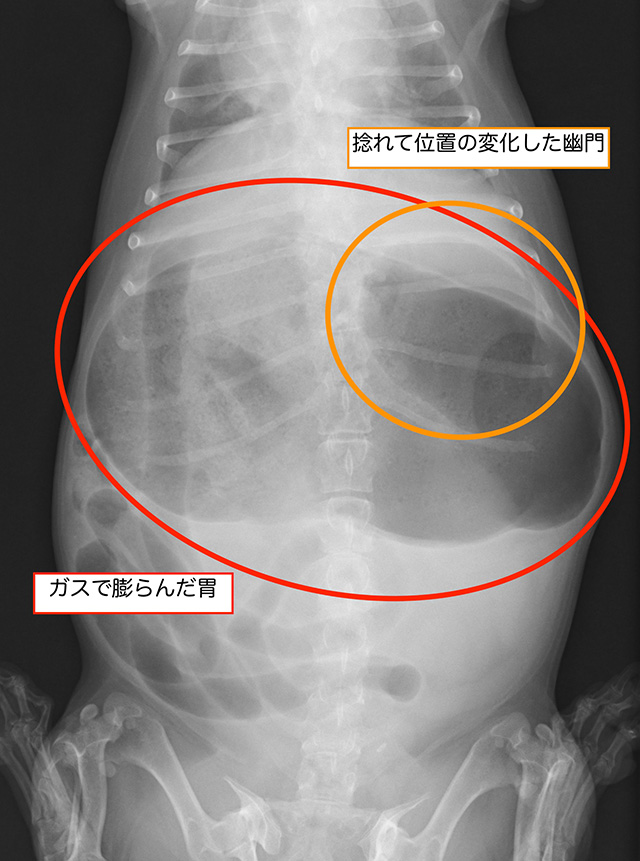

外観からもガスで膨らんだ胃が明らかですが、その他の病気との鑑別や捻転の有無などの判断にはX線検査が必要です。また、急性疾患であるため血液検査や心電図検査、超音波検査を駆使し、早期に病態を把握することが重要です。

X線検査です

胃がガスで大きく膨らんでいます

捻転を疑う所見もみられます